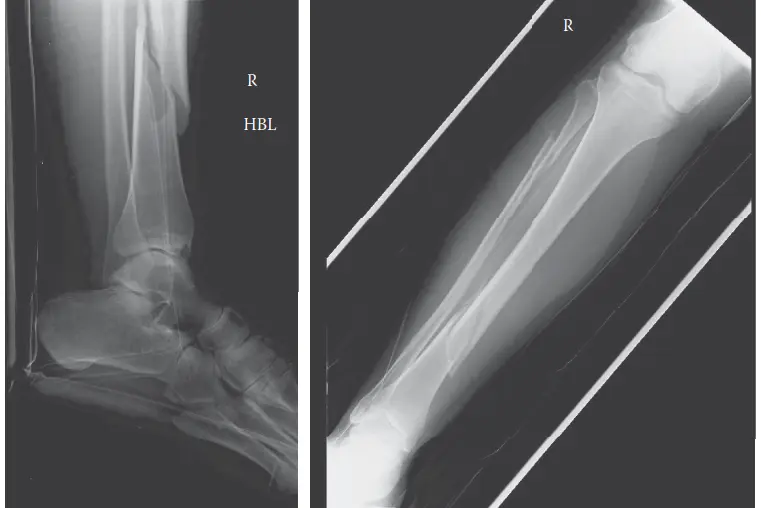

* الأشعة السينية (X-rays): تُجرى الأشعة السينية للطرف المصاب لتحديد وجود كسور عظمية وتصنيفها. لا تُظهر الأشعة السينية متلازمة الحيز نفسها، ولكنها ضرورية لتقييم الإصابة الأساسية.

صورة بالأشعة السينية تظهر كسرًا مفتتًا مائلًا حلزونيًا في منتصف عظم الساق الأيمن

الشكل 1: صورة بالأشعة السينية الجانبية تظهر كسرًا مفتتًا مائلًا حلزونيًا في منتصف عظم الساق الأيمن.